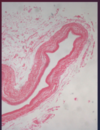

What is this structure and what is it comprised of?

Heart valve; core of fibroelastic CT, covered with endothelium

- What is this portion of the valve

- What is found lining heart valves (bottom arrow)?

- Cardiac/fibrous skeleton

- Endothelium